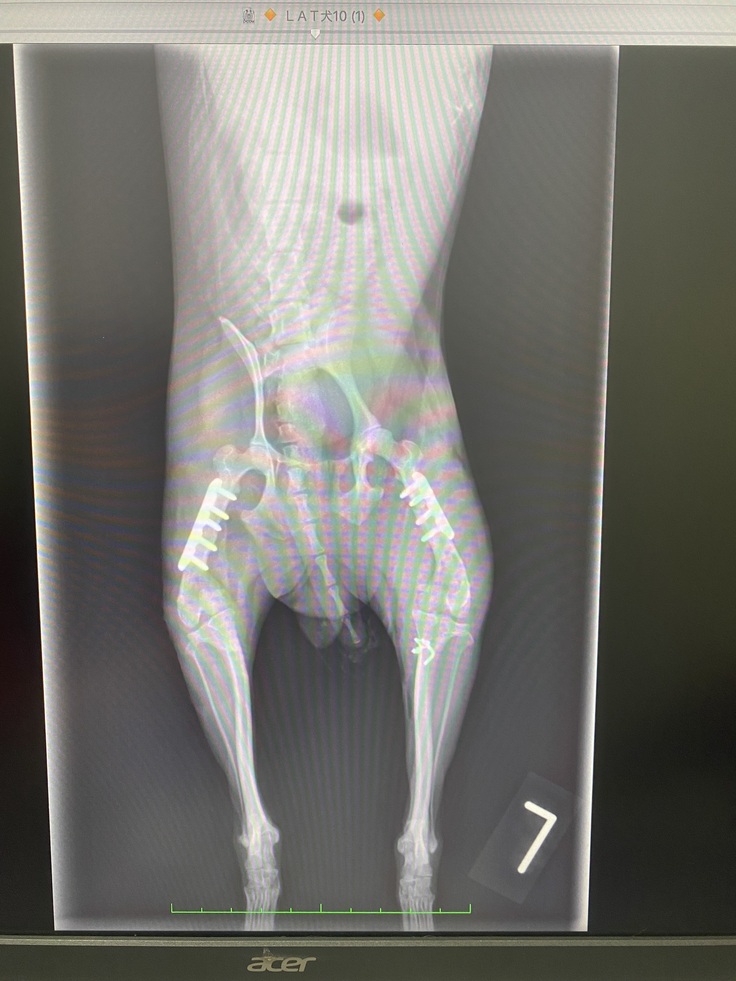

手術後のレントゲン写真

手術後のレントゲン写真です。

大腿骨部分切除したところを固定してるピンと別に、骨が細すぎるからとワイヤーでも固定してもらってます。